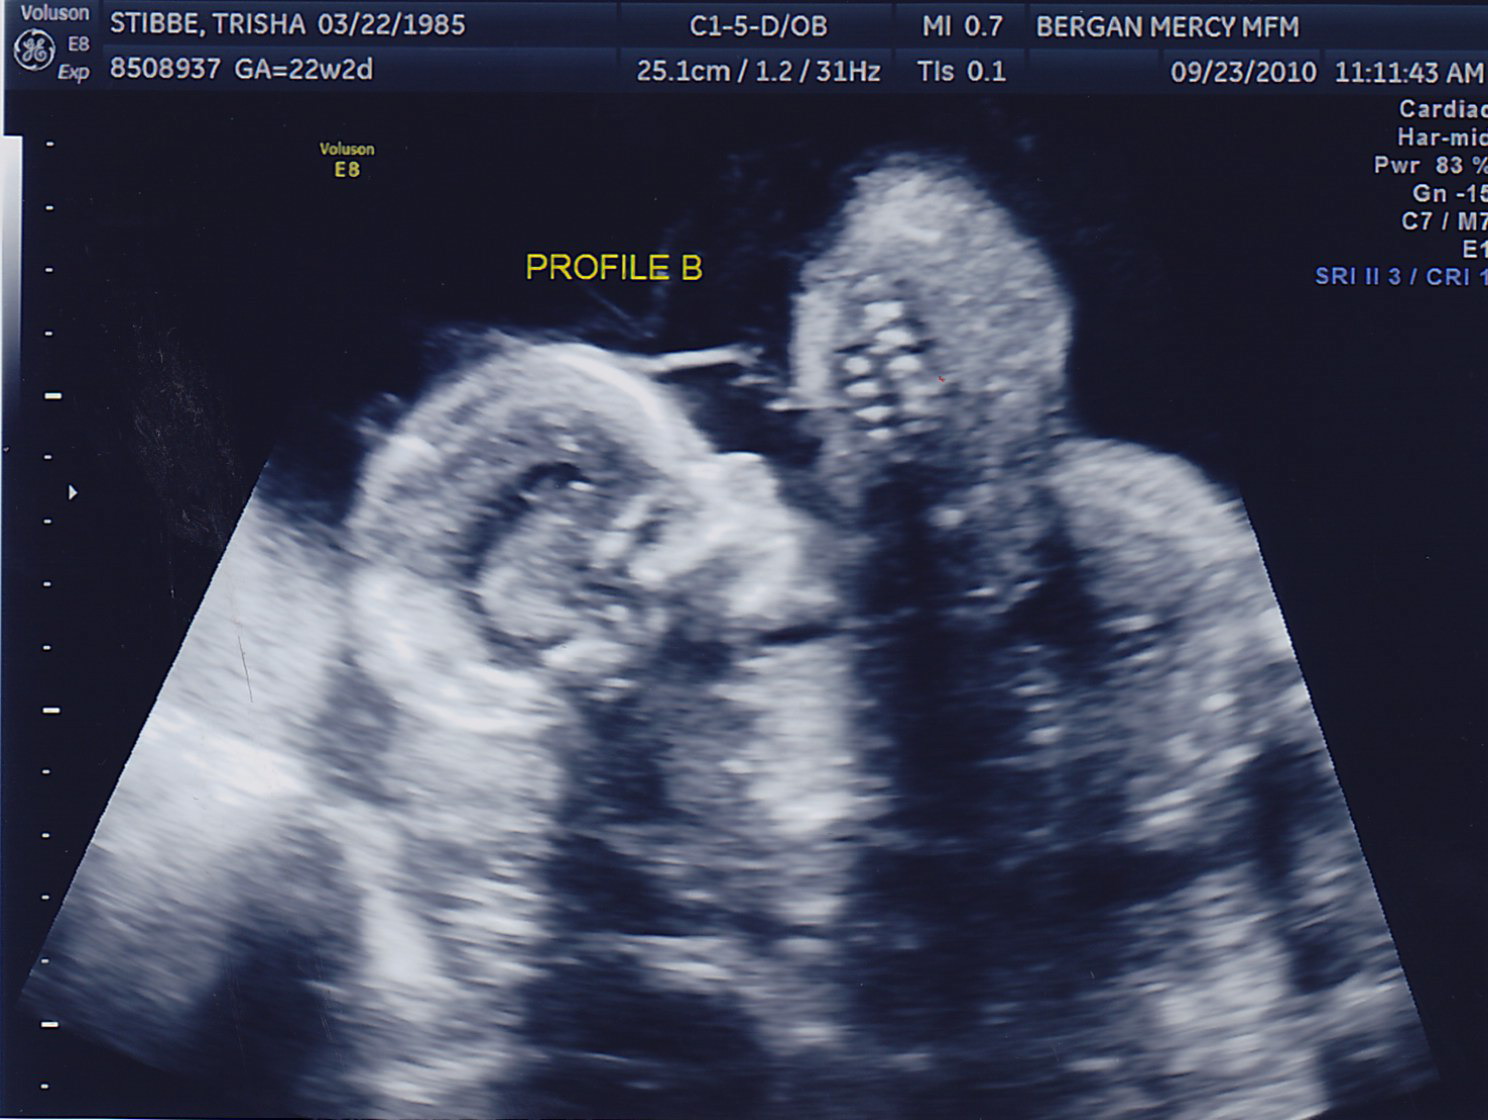

My sonographer Briana surprised me with 4D pictures! She was only able to get a good image of Baby A because Baby B is facing my back. One funny thing–for a while now they have both been on my right side and I could swear I looked lopsided. Then it started to kind of even out a little, and its because Baby A moved to the left! They’re finally learning to share 🙂 Last week they were both head down, and this week they’re both head up. Squirmy little guys.

Here are the little guys most recent pictures!

I just noticed that Baby B is a sports fan. I that that’s a football with him in the first picture. I hope he’s a Bison and Vikings fan. 😉